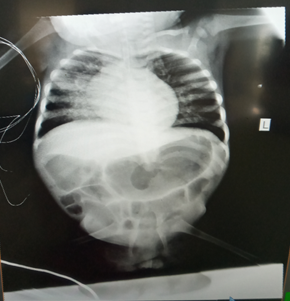

Chest x-ray was taken post- intubation, cardio- thoracic index was 0.54, no evidence of consolidation or pneumothorax seen, but moderate diffuse bilateral infiltrates. This x-ray helped us also, to understand the bone abnormalities, and we were capable to detect complete agenesis of the sacrum with a lumbar-iliac fusion (Figure 4). Echocardiography done showed ejection fraction of 42%, with mild mitral regurgitation and dilatation of the left ventricle. Renal/bladder ultrasound was ordered to assess if there is renal agenesis, or hypoplastic kidneys, and pronounced urinary bladder compatible with a neurogenic bladder.

Figure 4 Chest x-ray.